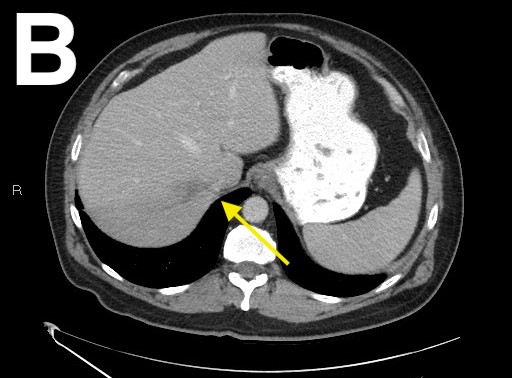

A bedside echocardiogram raised suspicion for vegetation of the anterior mitral valve leaflet. A computed tomography scan of the chest, abdomen, and pelvis revealed thrombosis of the right hepatic vein confirming results seen on the prior MRI scan, as well as diverticulosis with possible diverticular abscess at the level of the sigmoid colon (Figure 1).

Figure 2. A computed tomography scan of the abdomen and pelvis showed an unchanged right hepatic vein thrombosis (A-C) and a resolved diverticular abscess (D).